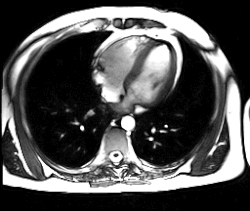

- L'IRM cardiaque est l'examen radiologique de référence pour l'exploration du muscle cardiaque lui-même, principalement pour les tumeurs cardiaques.